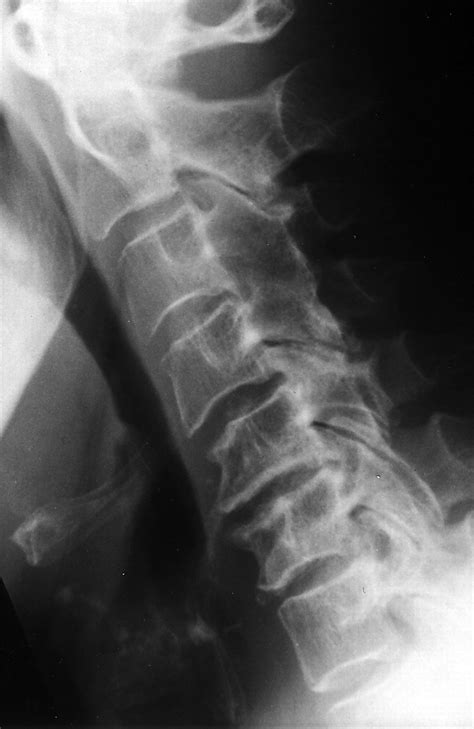

Arthritis in the neck occurs when the cartilage between the vertebrae in the cervical spine wears down, leading to inflammation and pain. This condition is often associated with aging but can also result from injuries, infections, or genetic factors. The most common types of arthritis affecting the neck are osteoarthritis and rheumatoid arthritis.

• Osteoarthritis: This is the most common type, caused by the wear and tear of the cartilage between the vertebrae.

• Imaging Tests: X-rays, MRI, or CT scans to visualize the bones and soft tissues in the neck.

These diagnostic tools help determine the type and severity of arthritis, guiding the appropriate treatment plan.